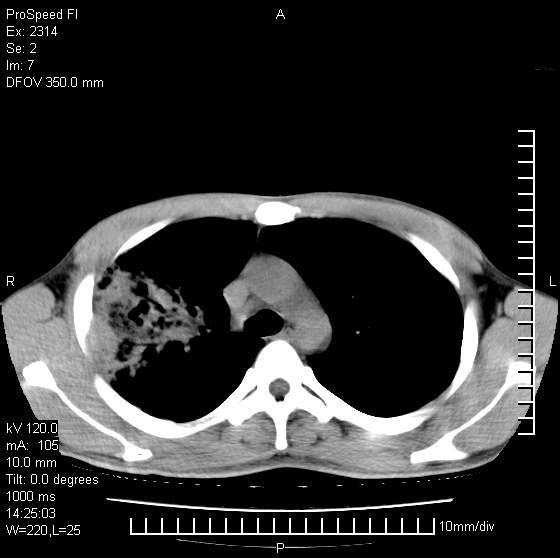

男性,再生障碍性贫血,入院前发热10天,最高40c,右侧胸痛,外院ct示右上,中肺边缘模糊的球性影(就是我现在图中标示的范围),考虑炎症,在我院使用头孢呋辛,洛美沙星10天,高烧消退,自感下午稍有发热,但今天ct示右上,中肺病灶明显扩大,还是考虑炎症,看其中的球型影是否霉菌感染??,是否能排除结核?

右肺中叶外侧段病变,上缘界限不清,下缘锐利,以段性发病为主,内见巨大空洞及空洞内容物,结合病史首先考虑:化脓性肺炎。不除外霉菌感染!

考虑霉菌感染.理由1\\有临床基础疾病,2\\有坏死的空腔,其内可见软组织影.

片状高密度影内见空洞影,内可见球形软组织密度影,并有新月征,考虑霉菌感染.